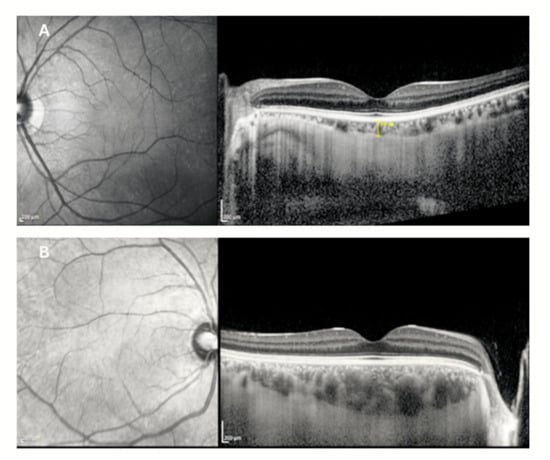

Background/Objectives: To evaluate the associations between corneal topographic irregularity, higher-order aberrations (HOAs), and posterior segment structural and microvascular parameters in keratoconus using optical coherence tomography (OCT) and OCT angiography (OCTA). Methods: In this cross-sectional study, 81 eyes with keratoconus and 60 healthy [...] Read more.

Background/Objectives: To evaluate the associations between corneal topographic irregularity, higher-order aberrations (HOAs), and posterior segment structural and microvascular parameters in keratoconus using optical coherence tomography (OCT) and OCT angiography (OCTA). Methods: In this cross-sectional study, 81 eyes with keratoconus and 60 healthy control eyes underwent corneal topography and wavefront analysis, spectral-domain OCT with enhanced depth imaging, and OCTA. Retinal layer thicknesses, choroidal thickness and area metrics, choroidal vascularity index (CVI), and OCTA-derived vascular parameters were analyzed. Associations were assessed using Spearman correlation analysis with false discovery rate (FDR) correction. Results: Compared with controls, keratoconus eyes showed significantly increased corneal curvature, corneal irregularity indices, and HOAs (all p < 0.001). Structural OCT analysis demonstrated preserved inner retinal layers, whereas outer nuclear layer thickness was reduced (p < 0.001) and overall outer retinal layer thickness was increased (p = 0.005). Choroidal thickness and both total and luminal choroidal areas were significantly greater in keratoconus eyes (all p ≤ 0.011), while CVI did not differ between groups (p > 0.05). OCTA revealed reduced superficial capillary plexus vessel density at the whole image and perifoveal regions (all p < 0.001), whereas deep capillary plexus and foveal avascular zone metrics were largely preserved. Correlation analyses identified only weak and inconsistent associations between corneal parameters, HOAs, and posterior segment measurements, none of which remained statistically significant after FDR correction. Conclusions: Despite pronounced anterior segment deformation and optical degradation, posterior segment structural and microvascular alterations in keratoconus are limited and weakly related to corneal disease severity. These findings support a predominantly anterior segment centered pathophysiology of keratoconus and highlight the importance of stringent multiple-comparison control in multimodal imaging studies. Full article

Figure 1